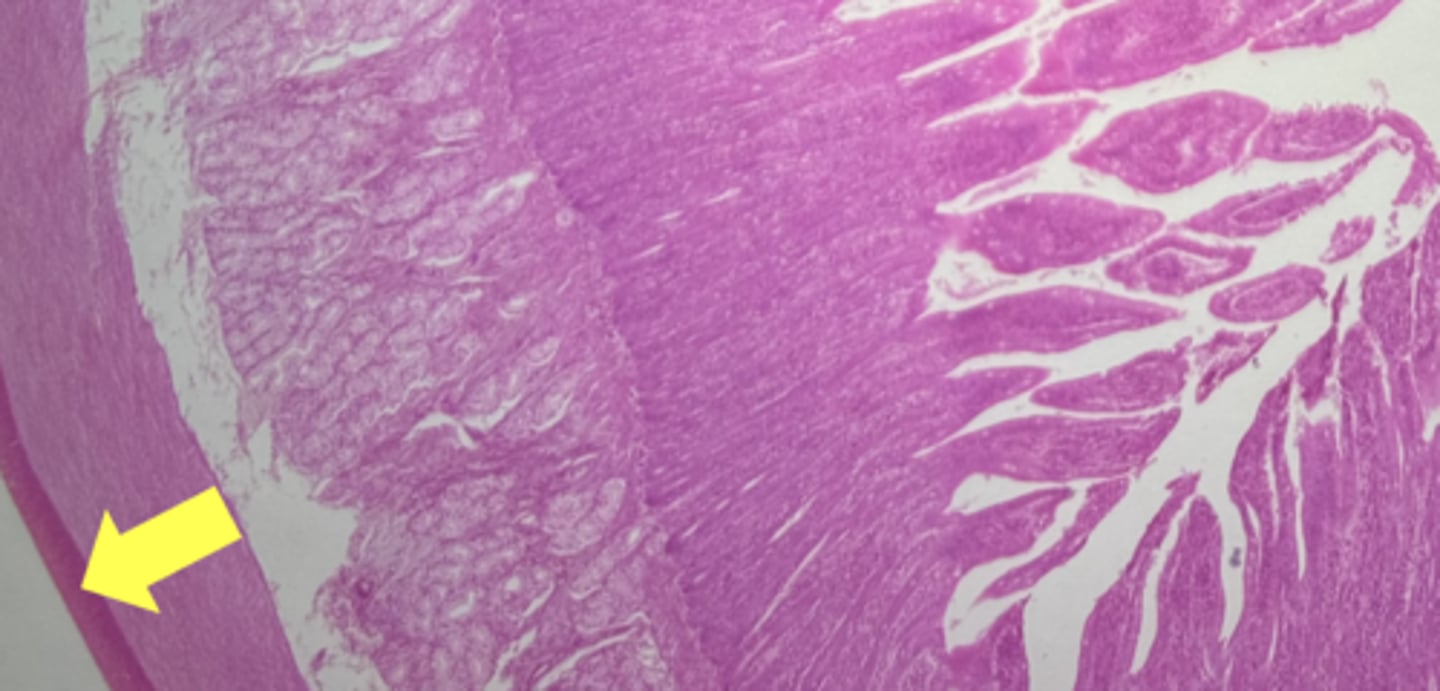

stomach

name the tissue

mucosa

(stomach)

submucosa

muscularis externa (3 LAYERS-KEY CHARACTERISTIC)

oblique layer

circular layer

longitudinal layer

simple columnar epithelium

gastric pits (KEY CHARACTERISTIC)

gastric glands (KEY CHARACTERISTIC)

Lamina propria

muscularis mucosae